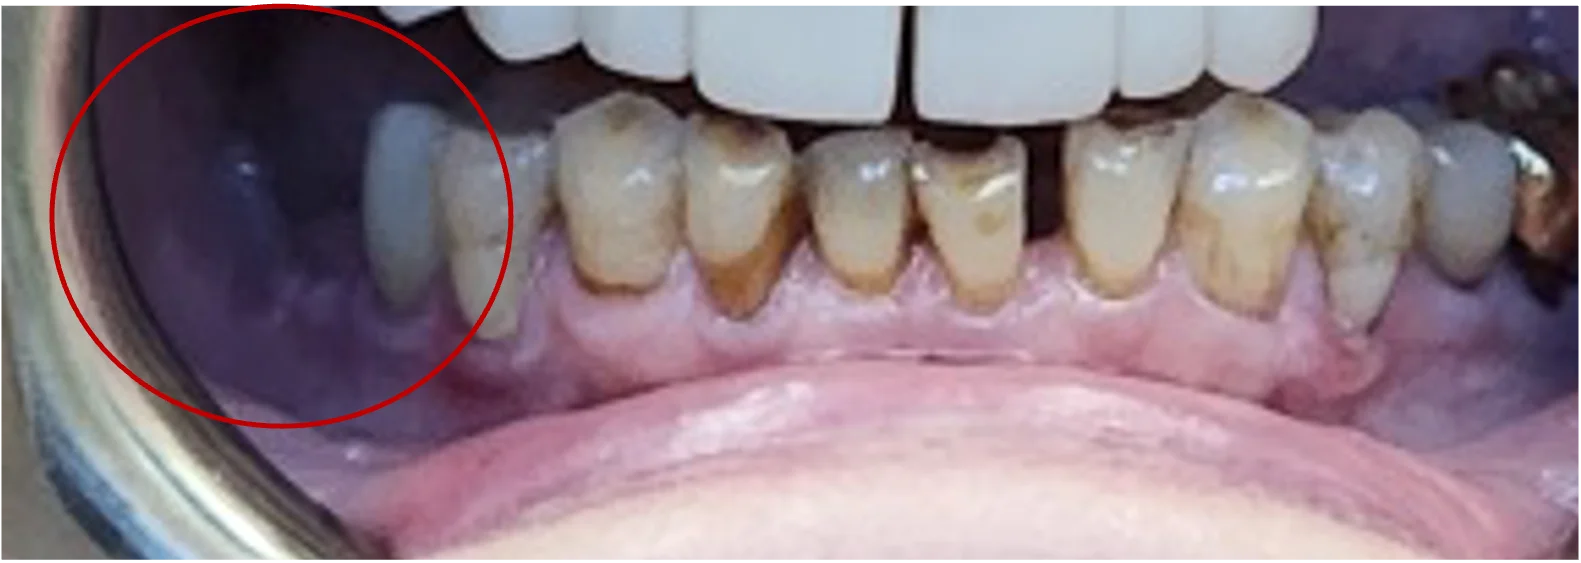

Congenitally missing tooth

Some patients are born without one or more adult teeth. Once jaw growth is complete, implants can offer a durable and natural-feeling replacement.